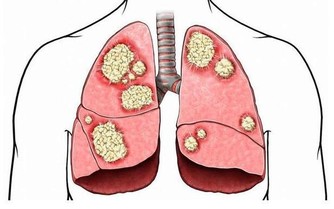

腫瘤部位不同,症狀也不同

同是大腸癌病友,但每個人的情況也會不一樣。

這是因為,長在不同部位的腫瘤,表現出來的症狀不一樣。

降結腸、乙狀結腸、直腸的癌症:腸道狹窄,再加上腸道蠕動活躍,就會出現便秘與腹瀉交替出現的情況。

還有,糞便通過時,會擦到腫瘤表面,引起出血。

癌症導致的出血若長期持續,就會出現貧血。

升結腸、橫結腸的癌症:症狀更難察覺。這些部位與小腸相連,小腸運來的糞便還處於液態,

即使此處有癌腫出血,出血量也不會太多,肉眼很難觀察到。

但如果出血時間長,會出現貧血,很多人都是出現貧血才發現大腸癌的。

所以,貧血是大腸癌的共同症狀。

另外,盲腸、升結腸、橫結腸中的癌腫變大後,撫摸肚子會感覺有小疙瘩或硬塊,

而在降結腸、乙狀結腸、直腸的位置,即使癌症處於進展期,也難以觸摸到疙瘩狀的腫塊。